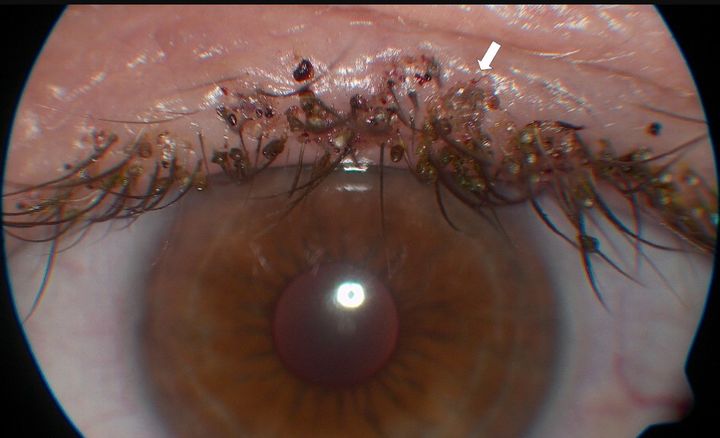

![[서울=뉴시스] 공개된 카미지 박사의 흉부 엑스레이 사진. (사진 = CBS콜로라도 캡처) 2025.09.30. *재판매 및 DB 금지](https://img1.newsis.com/2025/09/30/NISI20250930_0001957915_web.jpg?rnd=20250930142248)

[서울=뉴시스] 공개된 카미지 박사의 흉부 엑스레이 사진. (사진 = CBS콜로라도 캡처) 2025.09.30. *재판매 및 DB 금지

그러나 2022년 카미지 박사는 쌕쌕거리는 호흡과 어깨 통증으로 검사를 받던 중 4기 진행성 폐암 진단을 받았다. 당시 그는 단순한 천식이나 근육 손상 정도로 여겼지만, 불과 나흘 만에 불치 판정을 받게 됐다고 한다.